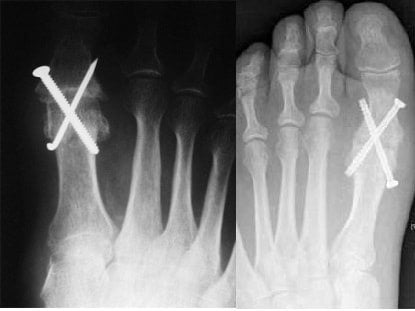

Выраженный артроз I плюсне-фалангового сустава приводит к резкому ограничению подвижности и ригидности большого пальца стопы. Рспространенным методом борьбы с этой проблемой является резекционная артропластика. В ходе оперативного вмешательства врачи удаляют костно-хрящевые разрастания и кистозные образования костной ткани. Также хирурги обязательно иссекают склерозированную капсулу сустава.

В клинической практике врачи используют несколько видов артропластики. Выбор определенной методики зависит от стадии артроза, характера деформации, возраста пациента, наличия у него сопутствующих заболеваний (плоскостопия, вальгусной деформации и т. д.).

На поздних стадиях остеоартроза врачи нередко выполняют артродезирование. Суть метода заключается в полном обездвиживании сустава путем его фиксации в определенном положении. После такой операции пациенту требуется продолжительная иммобилизация, которая длится 8-12 недель. К недостаткам артродеза можно отнести формирование костного блока, что в будущем приводит к перегрузке смежных суставов.